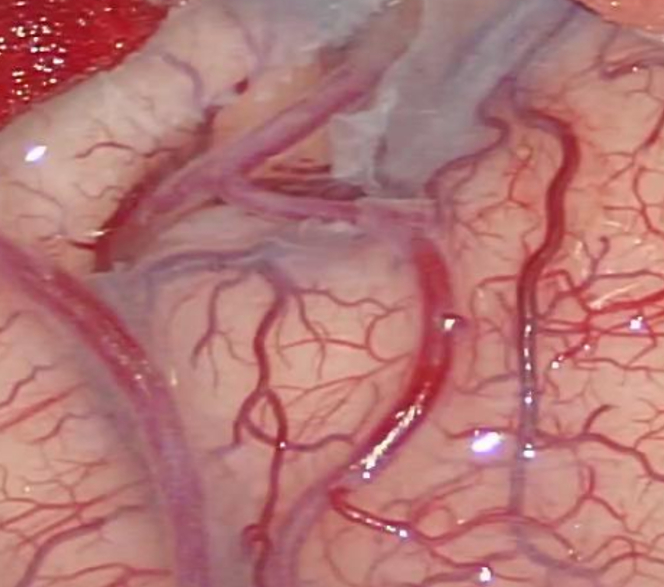

缝完血流通畅:

荧光造影显示血流通畅。挑起来看深入脑沟内的另一端(紧挨着的是根静脉):